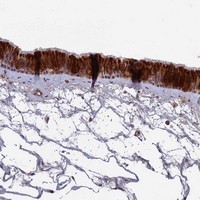

- Immunohistochemical staining of human nasopharynx with IGLON5 polyclonal antibody (Cat # PAB23886) shows strong cytoplasmic positivity in respiratory epithelial cells at 1:50-1:200 dilution.

- Immunohistochemistry (Formalin/PFA-fixed paraffin-embedded sections)